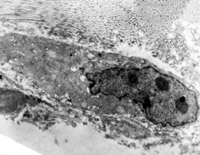

5-2-2 伤后第1天,毛细血管内皮细胞核固缩,管腔内血液凝集和瘀滞 TEM×6000